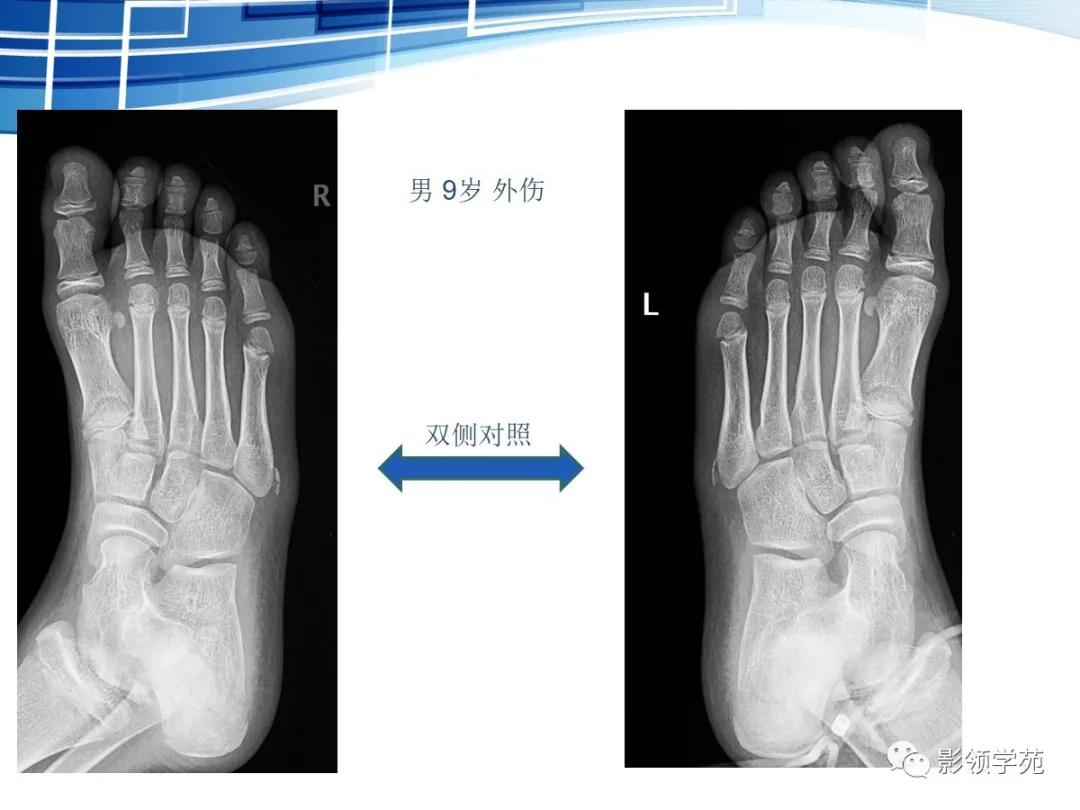

第五跖骨基底部骨折,常为横行骨折,即骨折线垂直于跖骨骨干,它是由于腓侧短肌肌腱应力所引起的撕脱骨折,也称“JONES骨折”。该骨折应与第五跖骨粗隆突起鉴别,尤其是9-15岁的儿童,常常可以出现第五跖骨基底部的骨骺,常表现为纵行透亮线,骨片边缘一般规则光滑,周围软组织无明显肿胀。

第五跖骨粗隆存在独立的骨化中心,并且可有一个或多个骨化中心,常见于10~15岁儿童。一般25岁左右与第五跖骨其余部分融合。

我们所常见的第五跖骨基底部骨折的骨折线一般都是垂直于长轴的,平行于第五跖骨长轴的骨折非常罕见。从外力方向、方式来发现,很难使第五跖骨基底部发生纵形骨折,而该处确实存在骨骺,大量的误诊就是把骨骺当骨折。

籽骨、副骨与永存骨骺一般边缘光滑, 周围皮质密度较高, 皮质光整, 附近骨质结构完整, 具有对称性, X线随诊形态及位置不会发生改变, 一般不会引起疼痛。但个别患者由于一些局部肌肉的扭伤而引起副骨的移位, 或由于机械外力的作用使副骨摩擦软组织导致滑囊炎和肌腱炎, 甚至由于长期慢性磨损可与附近正常骨质形成假关节从而产生创伤性关节炎可引起疼痛。而骨折一般具有明确的外伤史, 附近软组织肿胀明显, 疼痛症状明显, 断端锐利, 皮质断裂, 不具有对称性, X 线随诊形态及位置可发生移位。而籽骨、副骨与永存骨骺本身也可在外伤的情况下发生骨折, 但极罕见。

总之, 人体四肢关节易误诊的籽骨与副骨具有一定的好发部位及X线特征。全面了解对于降低临床误诊率有重要的意义。